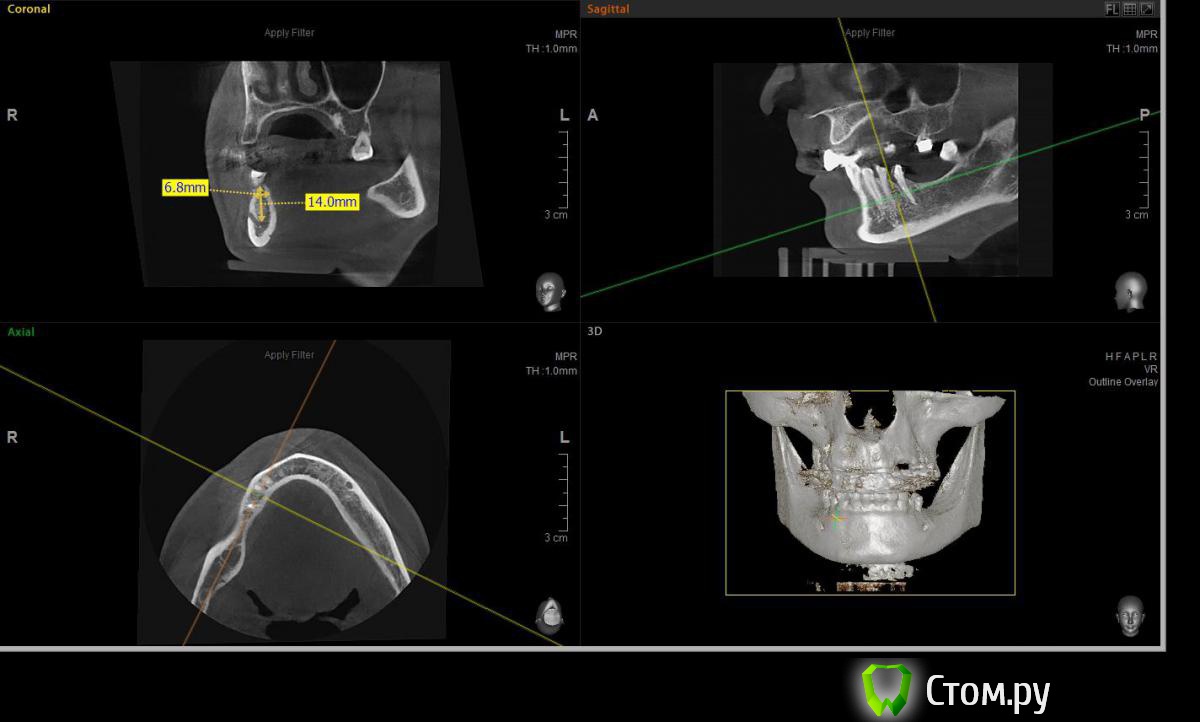

Евгений Ходыкин Опубликовано 2 июля, 2014 Автор Поделиться Опубликовано 2 июля, 2014 Замеры по 4.4 зубу: Ссылка на комментарий